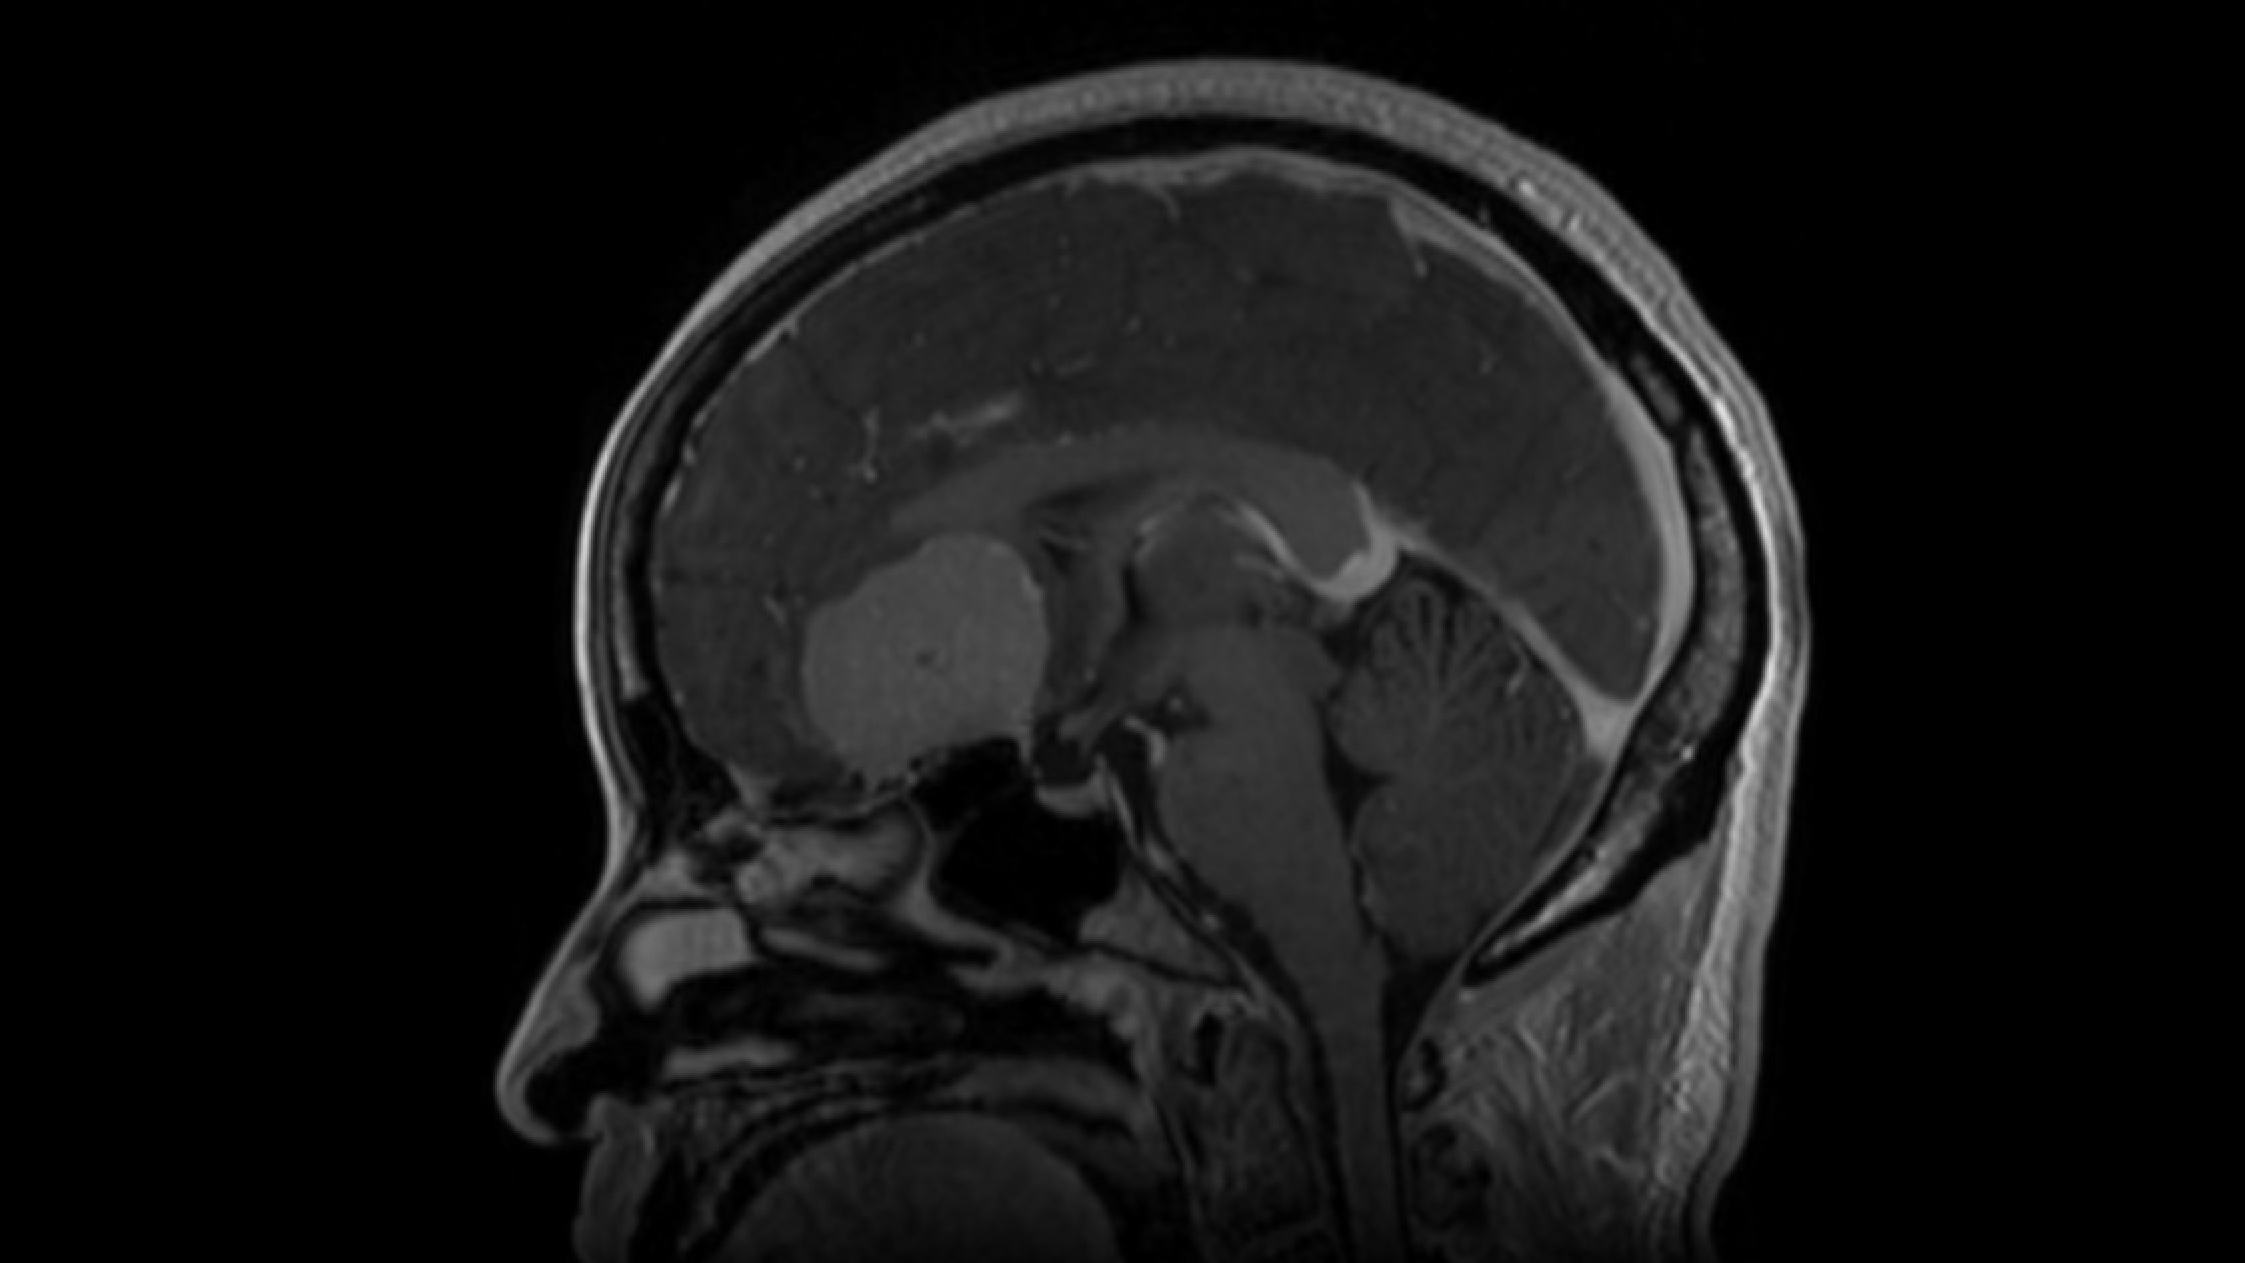

MRI scan showing a meningioma.